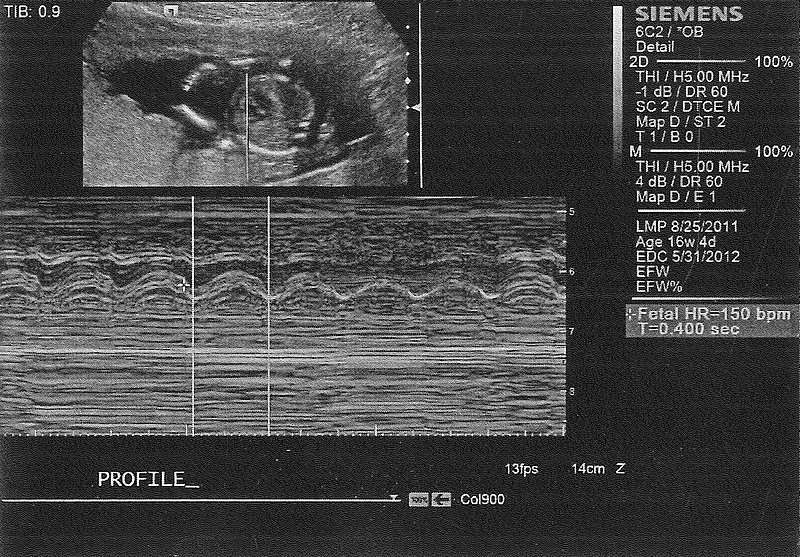

Profile of our baby.

Heart and heart beat.